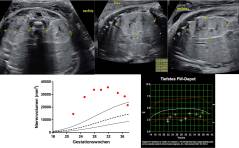

Sonoquiz - Was ist das?

Zuweisung in der 13. Woche zur Karyotypisierung mittels CVS bei pathologischer NT. PDF Dokument

Sonoquiz - Auflösung aus Ausgabe 03/19

Nierendysplasie bei Bardet-Biedl-Syndrom PDF Dokument